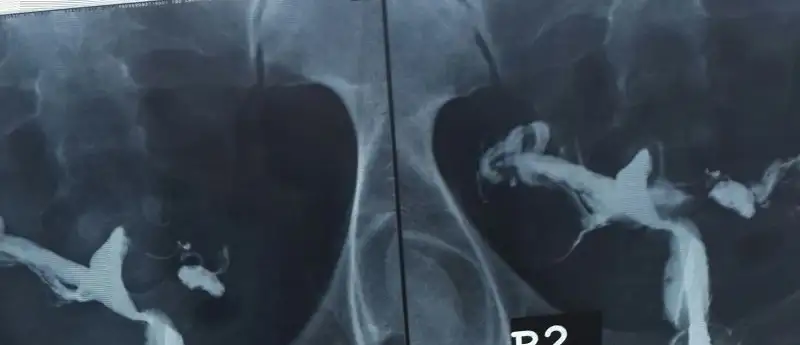

Evet canım gittim çok hafif bir çöküntü varmış rahim filmi iyi cekilmedigi için böyle teşhis konulmuş ayrıca uterus bicornis anomalisi hamileliğe asla engel değil senin durumdan daha kötü olan bir cok insana dogum yaptirdim dedi başarıcaz dedi sevgili doktorum şimdi klomene başlıycaz inşallah hayırlı bir sonuç alırım eğer gitmek istersen benim doktorumu tavsiye edebilirim kendisi beni doğurtan doktordu şimdide benim doktorum oldu konusunda uzman mükemmel bir insan

Hangi dr cnm.senin..ben internet uzerinde 4..5 dr yolladim hsg yi hepsi didrlfis drdi.hsg filmini cekip atsana resmini sana zahmet olmassa

Benimde bu geç oldu biraz ama çok yoğun günler geçirdim berbat çekilmiş bir filmmiş o yüzden net görünmüyor dr um çok inceledi eğer sanıldığı gibi olsaydı ilaç bu kadar dağılmazmış beyaz olan yerlerde ilaç azda olsa ulaşmış